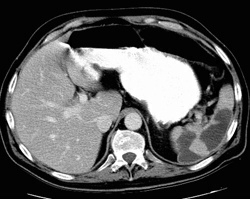

RADIOLOGY: SPLEEN: Case# 82: SPLENIC & RENAL INFARCTS; SPLENIC VEIN THROMBOSIS. 47 year old gentleman with Crohns disease. Comparison is made with a prior CT. Todays study demonstrates large wedged shaped defects through the spleen which are homogeneously low in attenuation and well circumscribed. The splenic vein is enlarged with peripheral rim of contrast and centrally low attenuation noted to the level of the approximately the confluence with the inferior mesenteric vein. The portal- splenic confluence in portal appear patent by CT. The SMV appears patent as well. Small, well-defined low attenuation defects are also noted in the kidneys peripherally.